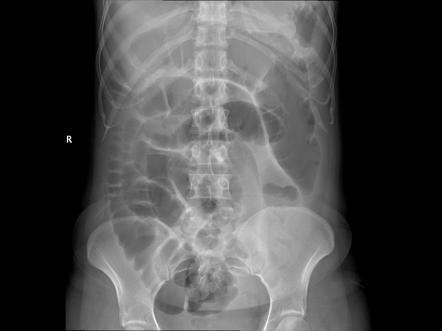

Small bowel obstruction

valvulae conniventes confirm it’s small bowel